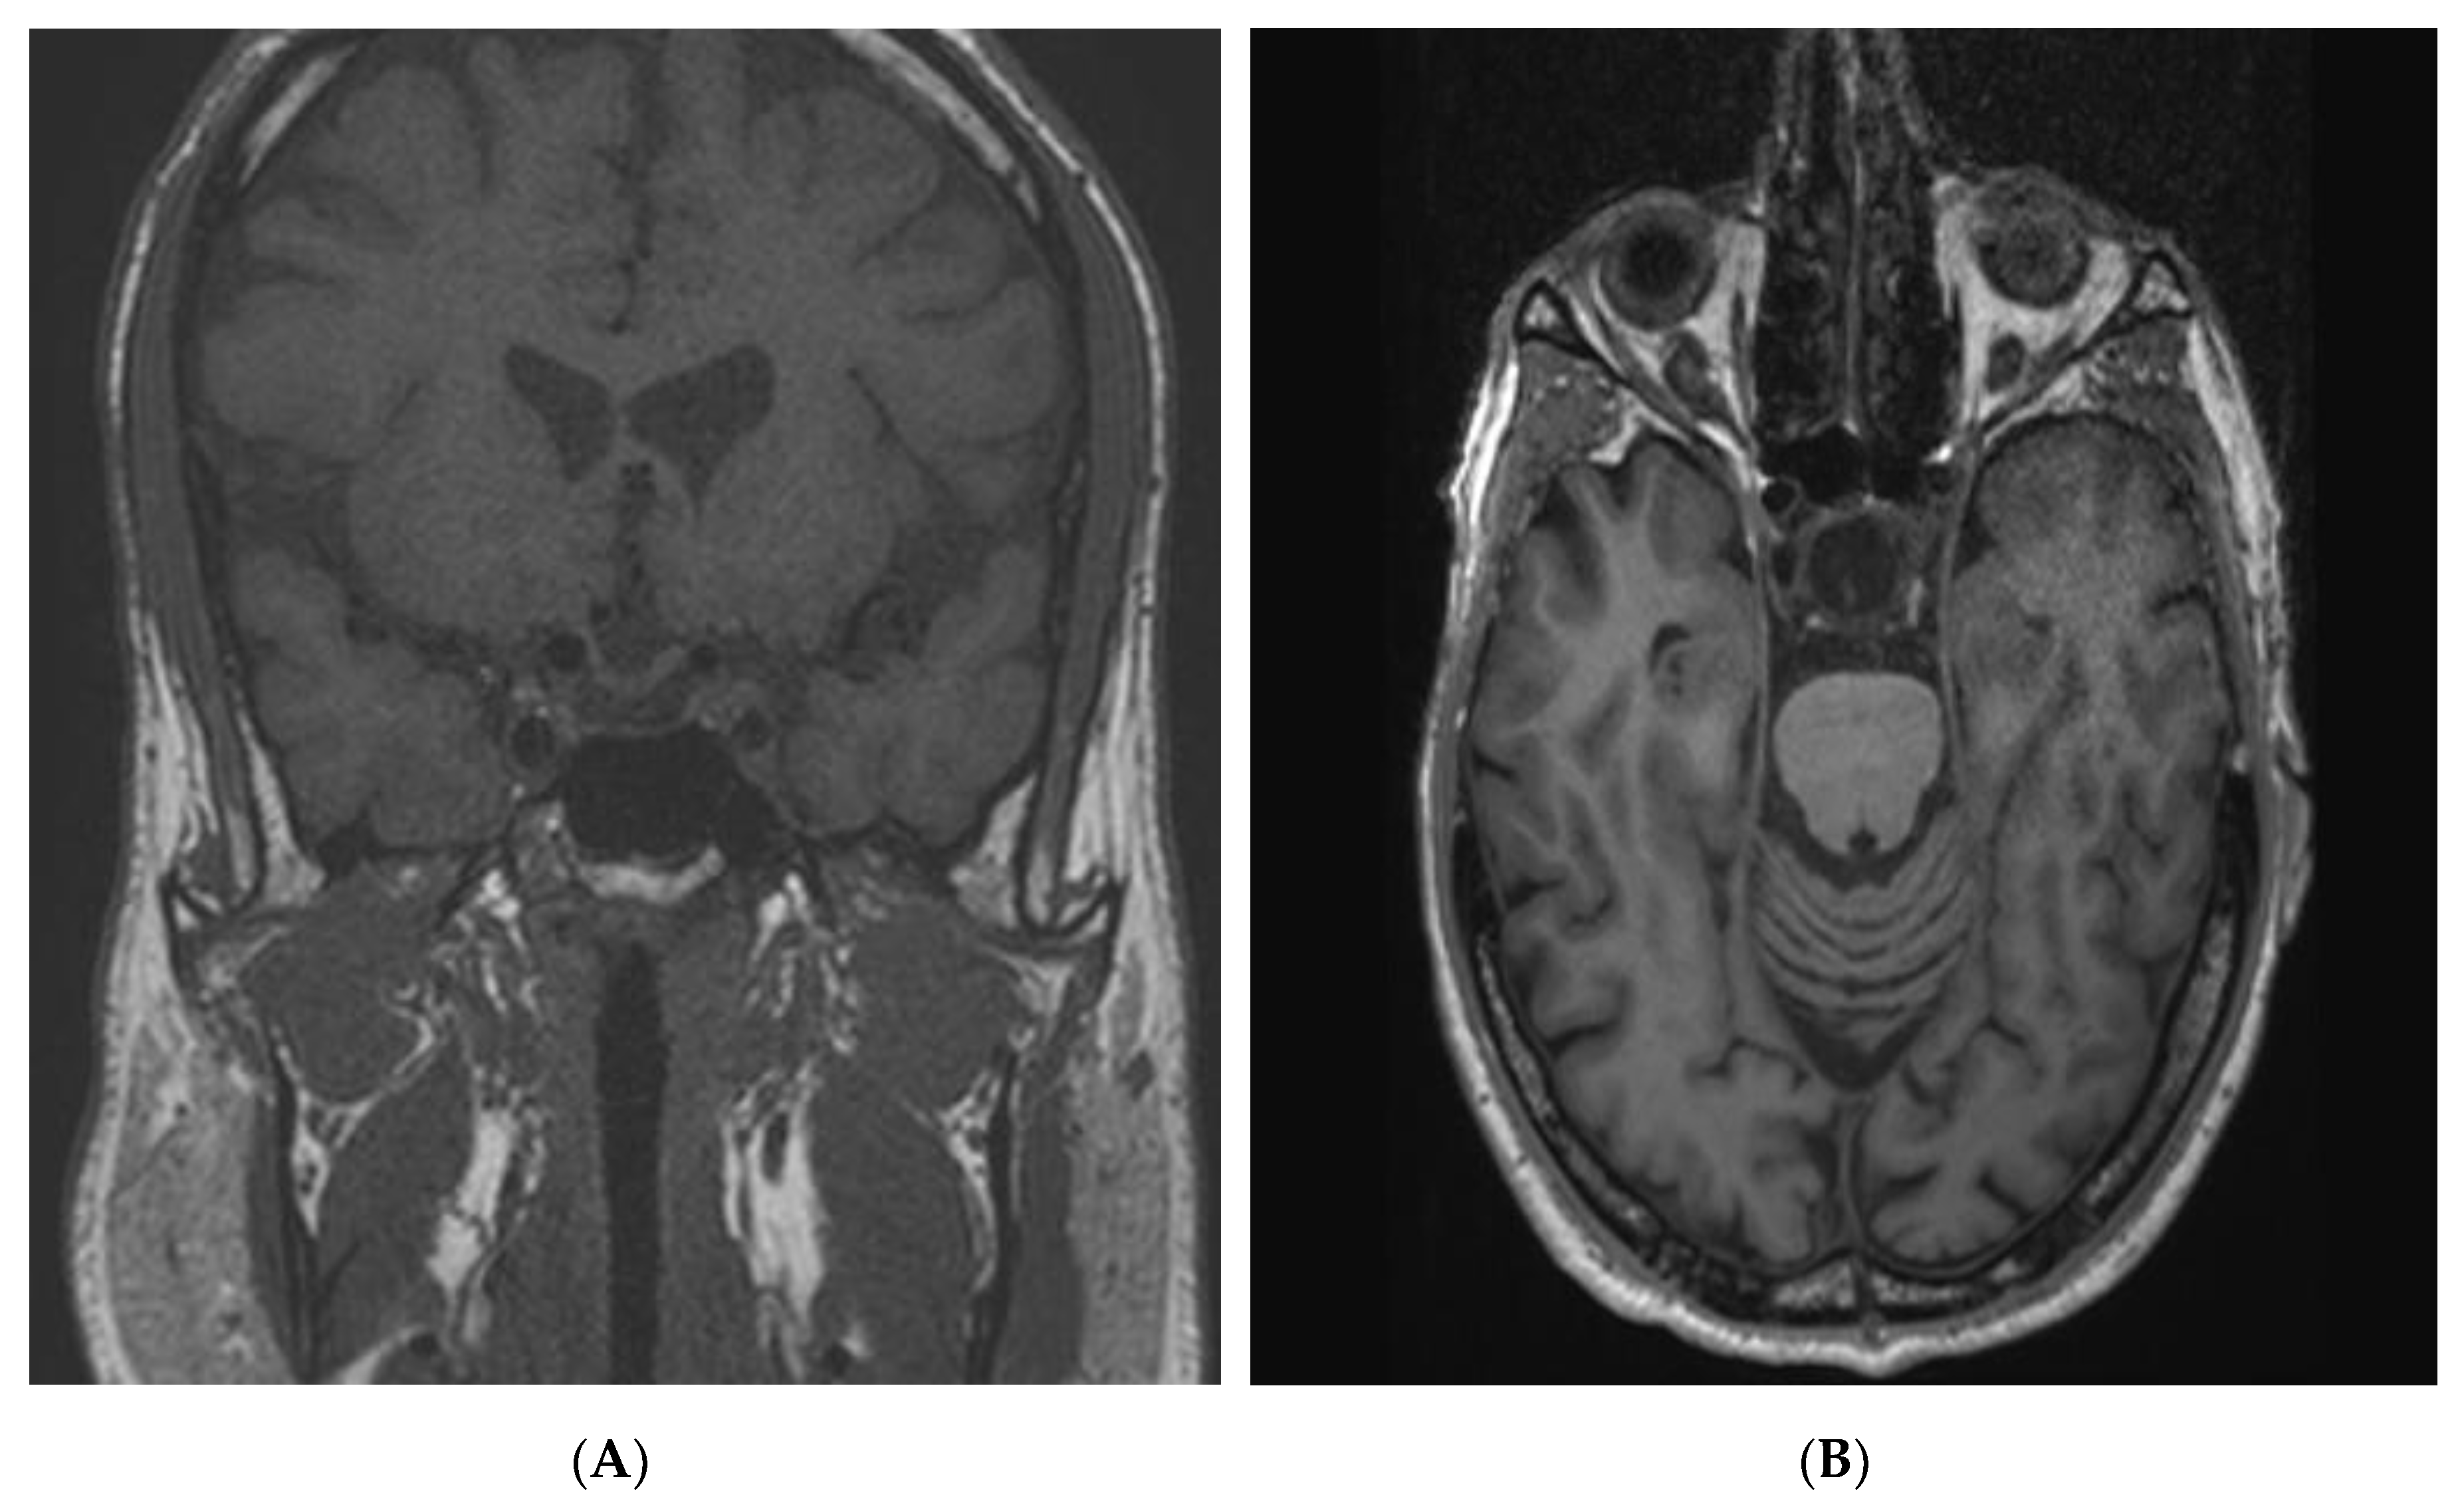

2.3. Acromegaly

2.4. Prolactinoma and mixed tumors

2.5. Non-Functioning Pituitary Adenomas

2.6. Pituitary Apoplexy and Other Tumors in AIP Mutation-Positive Patients